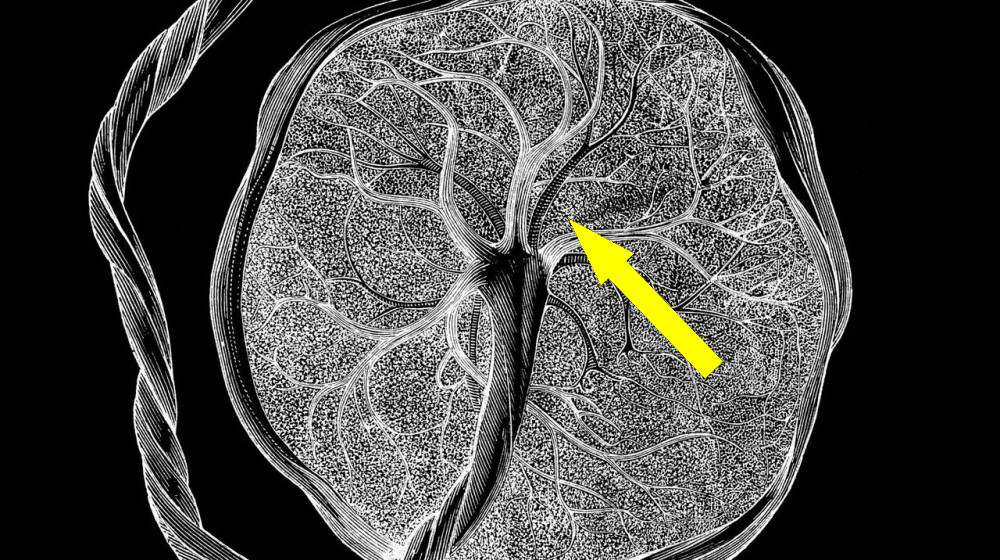

Аппендикс оказался куда важнее, чем думали ученые

Несмотря на долгое время считавшийся рудиментом и «ненужной» частью человеческого организма, аппендикс продолжает удивлять исследователей. Недавние научные открытия доказали, что этот небольшой о...